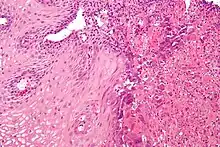

Upper Endoscopy often reveals ulcers throughout the esophagus with intervening normal-appearing mucosa. In severe cases the ulcers can coalesce and on rare occasions have a black appearance known as black esophagus.[8] While the diagnosis of herpes esophagitis can be inferred clinically it can only be accurately diagnosed through endoscopically obtained biopsies with microscopic evaluation by a pathologist finding the appropriate inclusion bodies and diagnostic immunochemical staining.[9] False negative findings may occur if biopsies are taken from the ulcer rather than from the margin of the ulcer as the inclusion particles are to be found in viable epithelial cells. Viral tissue culture represents the most accurate means of diagnosing the precise cause.